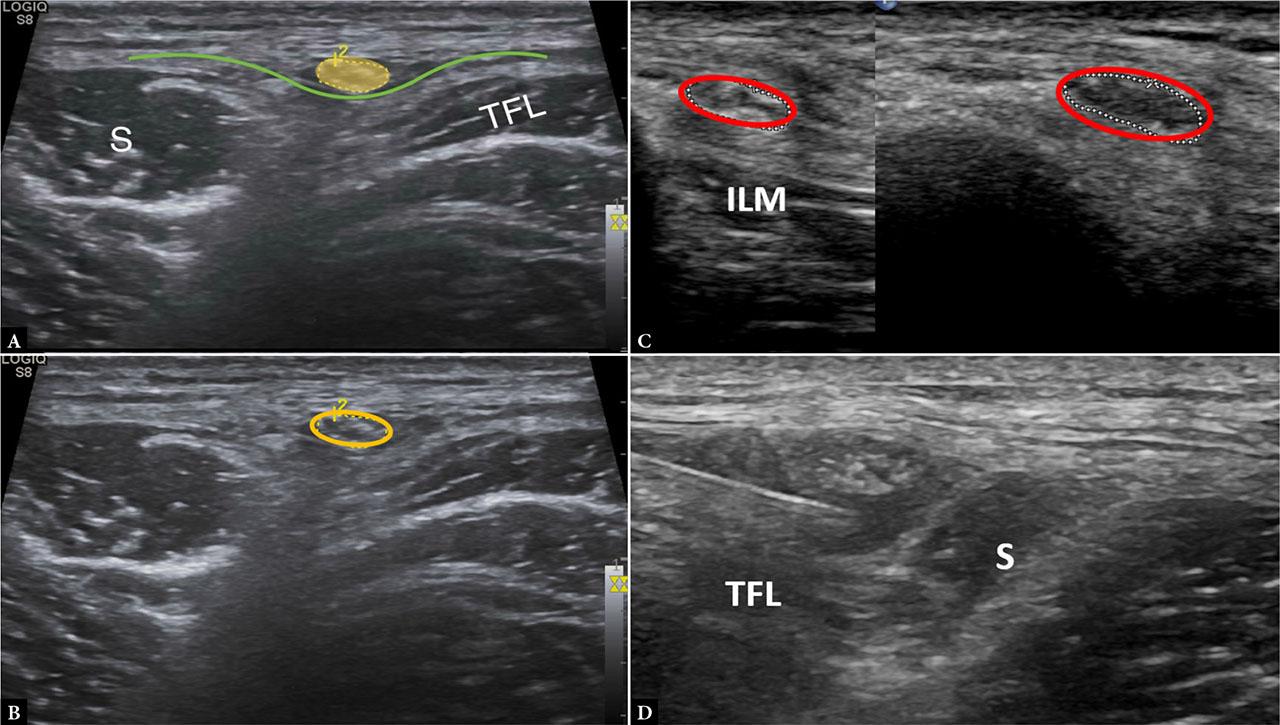

The lateral femoral cutaneous nerve (LFCN), a purely sensory branch of the lumbar plexus, emerges from the lateral border of the psoas major, crosses the iliacus, and usually passes beneath the inguinal ligament near the anterior superior iliac spine (ASIS). Its variable course makes ultrasound an ideal modality for localization. With the patient supine, a high-frequency linear probe is placed transversely at the ASIS. The nerve is typically seen between the sartorius and tensor fasciae lata muscles, appearing as a small hypoechoic fascicular structure superficial to the muscular fascia, and it can be traced proximally toward the inguinal ligament. Sonographic identification is particularly useful in meralgia paresthetica, where the nerve may appear thickened or hypoechoic at the site of entrapment, usually as it courses under the inguinal ligament at the groin crease. Ultrasound also improves the accuracy of targeted perineural injections(19,20,21) (Fig. 9).

Images A and B demonstrate the lateral femoral cutaneous nerve (yellow circle) superficial to the muscular fascia (green), lying between the sartorius (S) anteriorly and the tensor fascia lata (TFL) posteriorly. Image C shows thickening of the LFCN as it crosses the inguinal ligament (encircled). The normal proximal caliber of the LFCN can be seen at the level of the iliacus muscle (ILM). Image D demonstrates ultrasound-guided perineural hydrodissection of the LFCN as it courses superficial to the muscular fascia between the TFL and sartorius